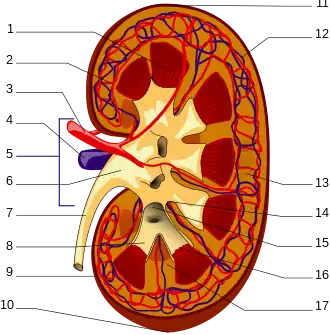

Innerer Aufbau: Rinde und Mark

1. Nierenmark mit Markkegeln (Pyramides renales)

2. Vas afferens

3. Nierenarterie (Arteria renalis)

4. Nierenvene (Vena renalis)

5. Hilum renale

6. Nierenbecken (Pelvis renalis)

7. Harnleiter (Ureter)

8. kleine Nierenkelche (Calices minores renales)

9. Nierenkapsel (Capsula fibrosa renalis)

10. unterer Nierenpol (Extremitas inferior)

11. oberer Nierenpol (Extremitas superior)

12. Vas efferens

13. Nephron

14. Nierenbucht (Sinus renalis)

15. große Nierenkelche (Calices majores renales)

16. Spitzen der Markkegel (Papillae renales)

17. Bertin-Säule (Columna renalis)

Das Nierenparenchym, die eigentliche Organmasse der Niere, wird in die außen liegende Nierenrinde (Cortex renalis) und das nach innen zum Hilum gerichtete Nierenmark (Medulla renalis) unterteilt. Das Mark besitzt dabei die Form von Pyramiden (10 bis 12 Markpyramiden oder Nierenpyramiden), die mit ihrer Basis nach außen und mit ihrer Spitze nach innen zum Hilum zeigen. Diese Spitzen, die Papillen, reichen frei in den Hohlraum der Nierenkelche (Calix renalis), die sich in variabler Form zum Nierenbecken (Pelvis renalis) zusammenschließen, aus dem der Ureter hervorgeht. In dieser Anordnung fließt der Urin aus den Papillen in Richtung Ureter.

Die Nierenrinde liegt wie eine Kappe zwischen den Basen der Markpyramiden und der Organkapsel (subkapsulärer Anteil), erreicht aber zwischen den Pyramiden in säulenförmigen Abschnitten (Columnae renales, nach dem französischen Anatomen Exupère Joseph Bertin[10] seit 1744 auch Columnae renales Bertini oder Bertinsche Säulen genannt) den Sinus renalis. Der subkapsuläre Anteil der Rinde wird von gut sichtbaren, feinen Strichen durchzogen, den Markstrahlen (Radii medullares), die radiär aus den Markpyramiden in Richtung der Organkapsel ausstrahlen und Teil des Marks sind. Im Mark selbst lassen sich durch ihre leicht unterschiedliche Farbe ein äußeres Mark, bestehend aus einem Außen- und einem Innenstreifen, und ein zum Nierenbecken gelegenes inneres Mark unterscheiden.